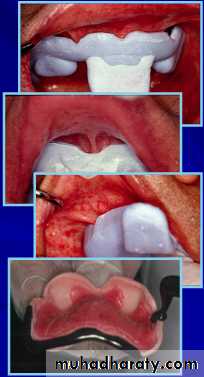

Border MoldingThe shaping of the border areas of an impression tray by functional or manual manipulation of the tissue adjacent to the borders to duplicate the contour and size of the vestibule.

Adjusting Maxillary Custom Tray

Reduce the flanges of the tray 2 mm short from the sulcusAdjust labial frenal attachment

Adjust buccal frenal attachmentDo not remove the wax spacer until final impression is made

The posterior border of the custom tray must cover the hamular notches and extended approximately (2 mm) posterior to the vibrating line across the palate.Border Molding

Soften the modeling plastic impression compound over the alcohol torch flame and place it over the border of the tray.After tempering in water bath at 70 F, border mold it in the mouth.

Border Molding Labial Sulcus

In the region of labial sulcus, the upper lip is elevated and extended out and then pulled downward and inward.Re-soften the compound and repeat this procedure to establish proper border molding.

Border Molding Buccal Sulcus

In the region of buccal frenum, the cheek is elevated and then pulled outward, downward and inward.Move the cheek backward and forward to simulate movement of buccal frenum as in function during eating and smiling

Border Molding Buccal Sulcus at Tuberosity

The posterior buccal flange at the tuberosity region is border molded when the cheek is extended outward, downward and inward.with the tray in place, have the patient open mouth widely and move the jaw laterally to establish the width of the sulcus.

Making Final Impression

The mixed impression material is placed on the tray with borders coverd.

Seat the tray in the mouth and border mold in the posterior region first and then in the anterior region.

Do not load the tray with excess of material.

Final Rubber Base Impression with Outline Landmarks

1. Labial frenum2. Labial flange

3. Buccal frenum

4. Buccal flange

5. Pteromandibular raphe

6. Fovea palatinae

7. Vibrating line